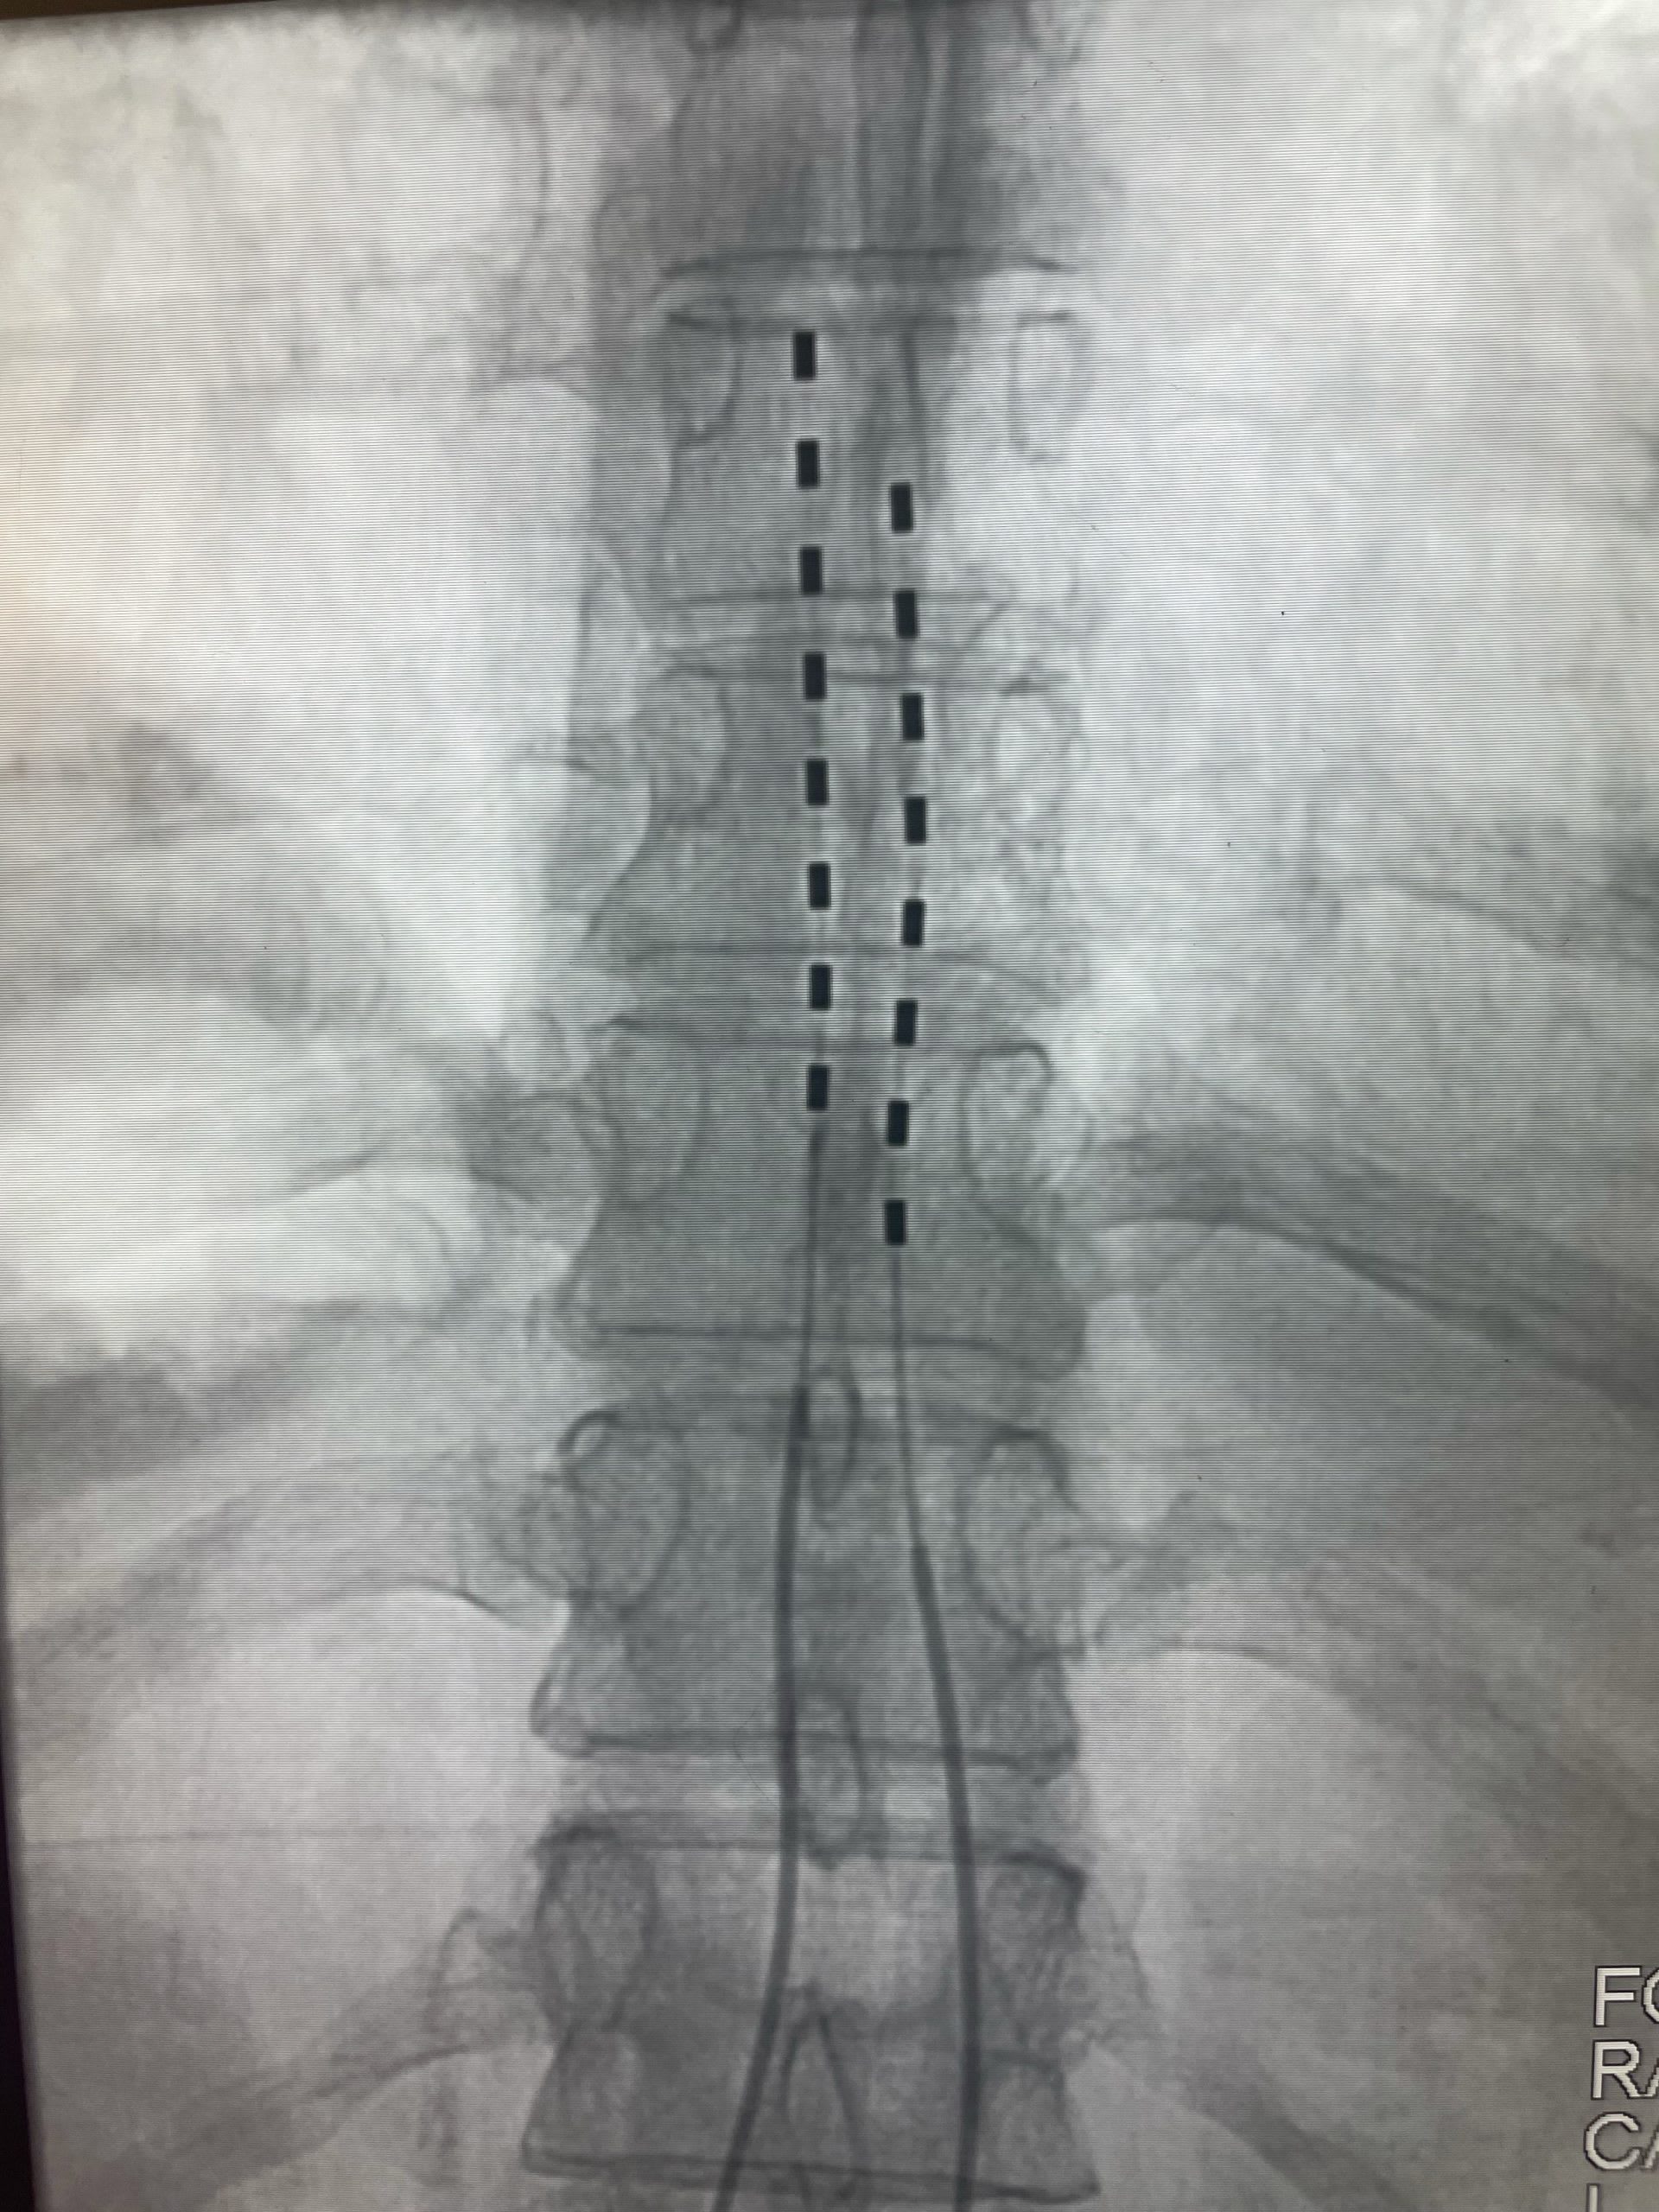

LATIS® Transforaminal Lumbar Interbody (TLIF) Spacer Globus Medical